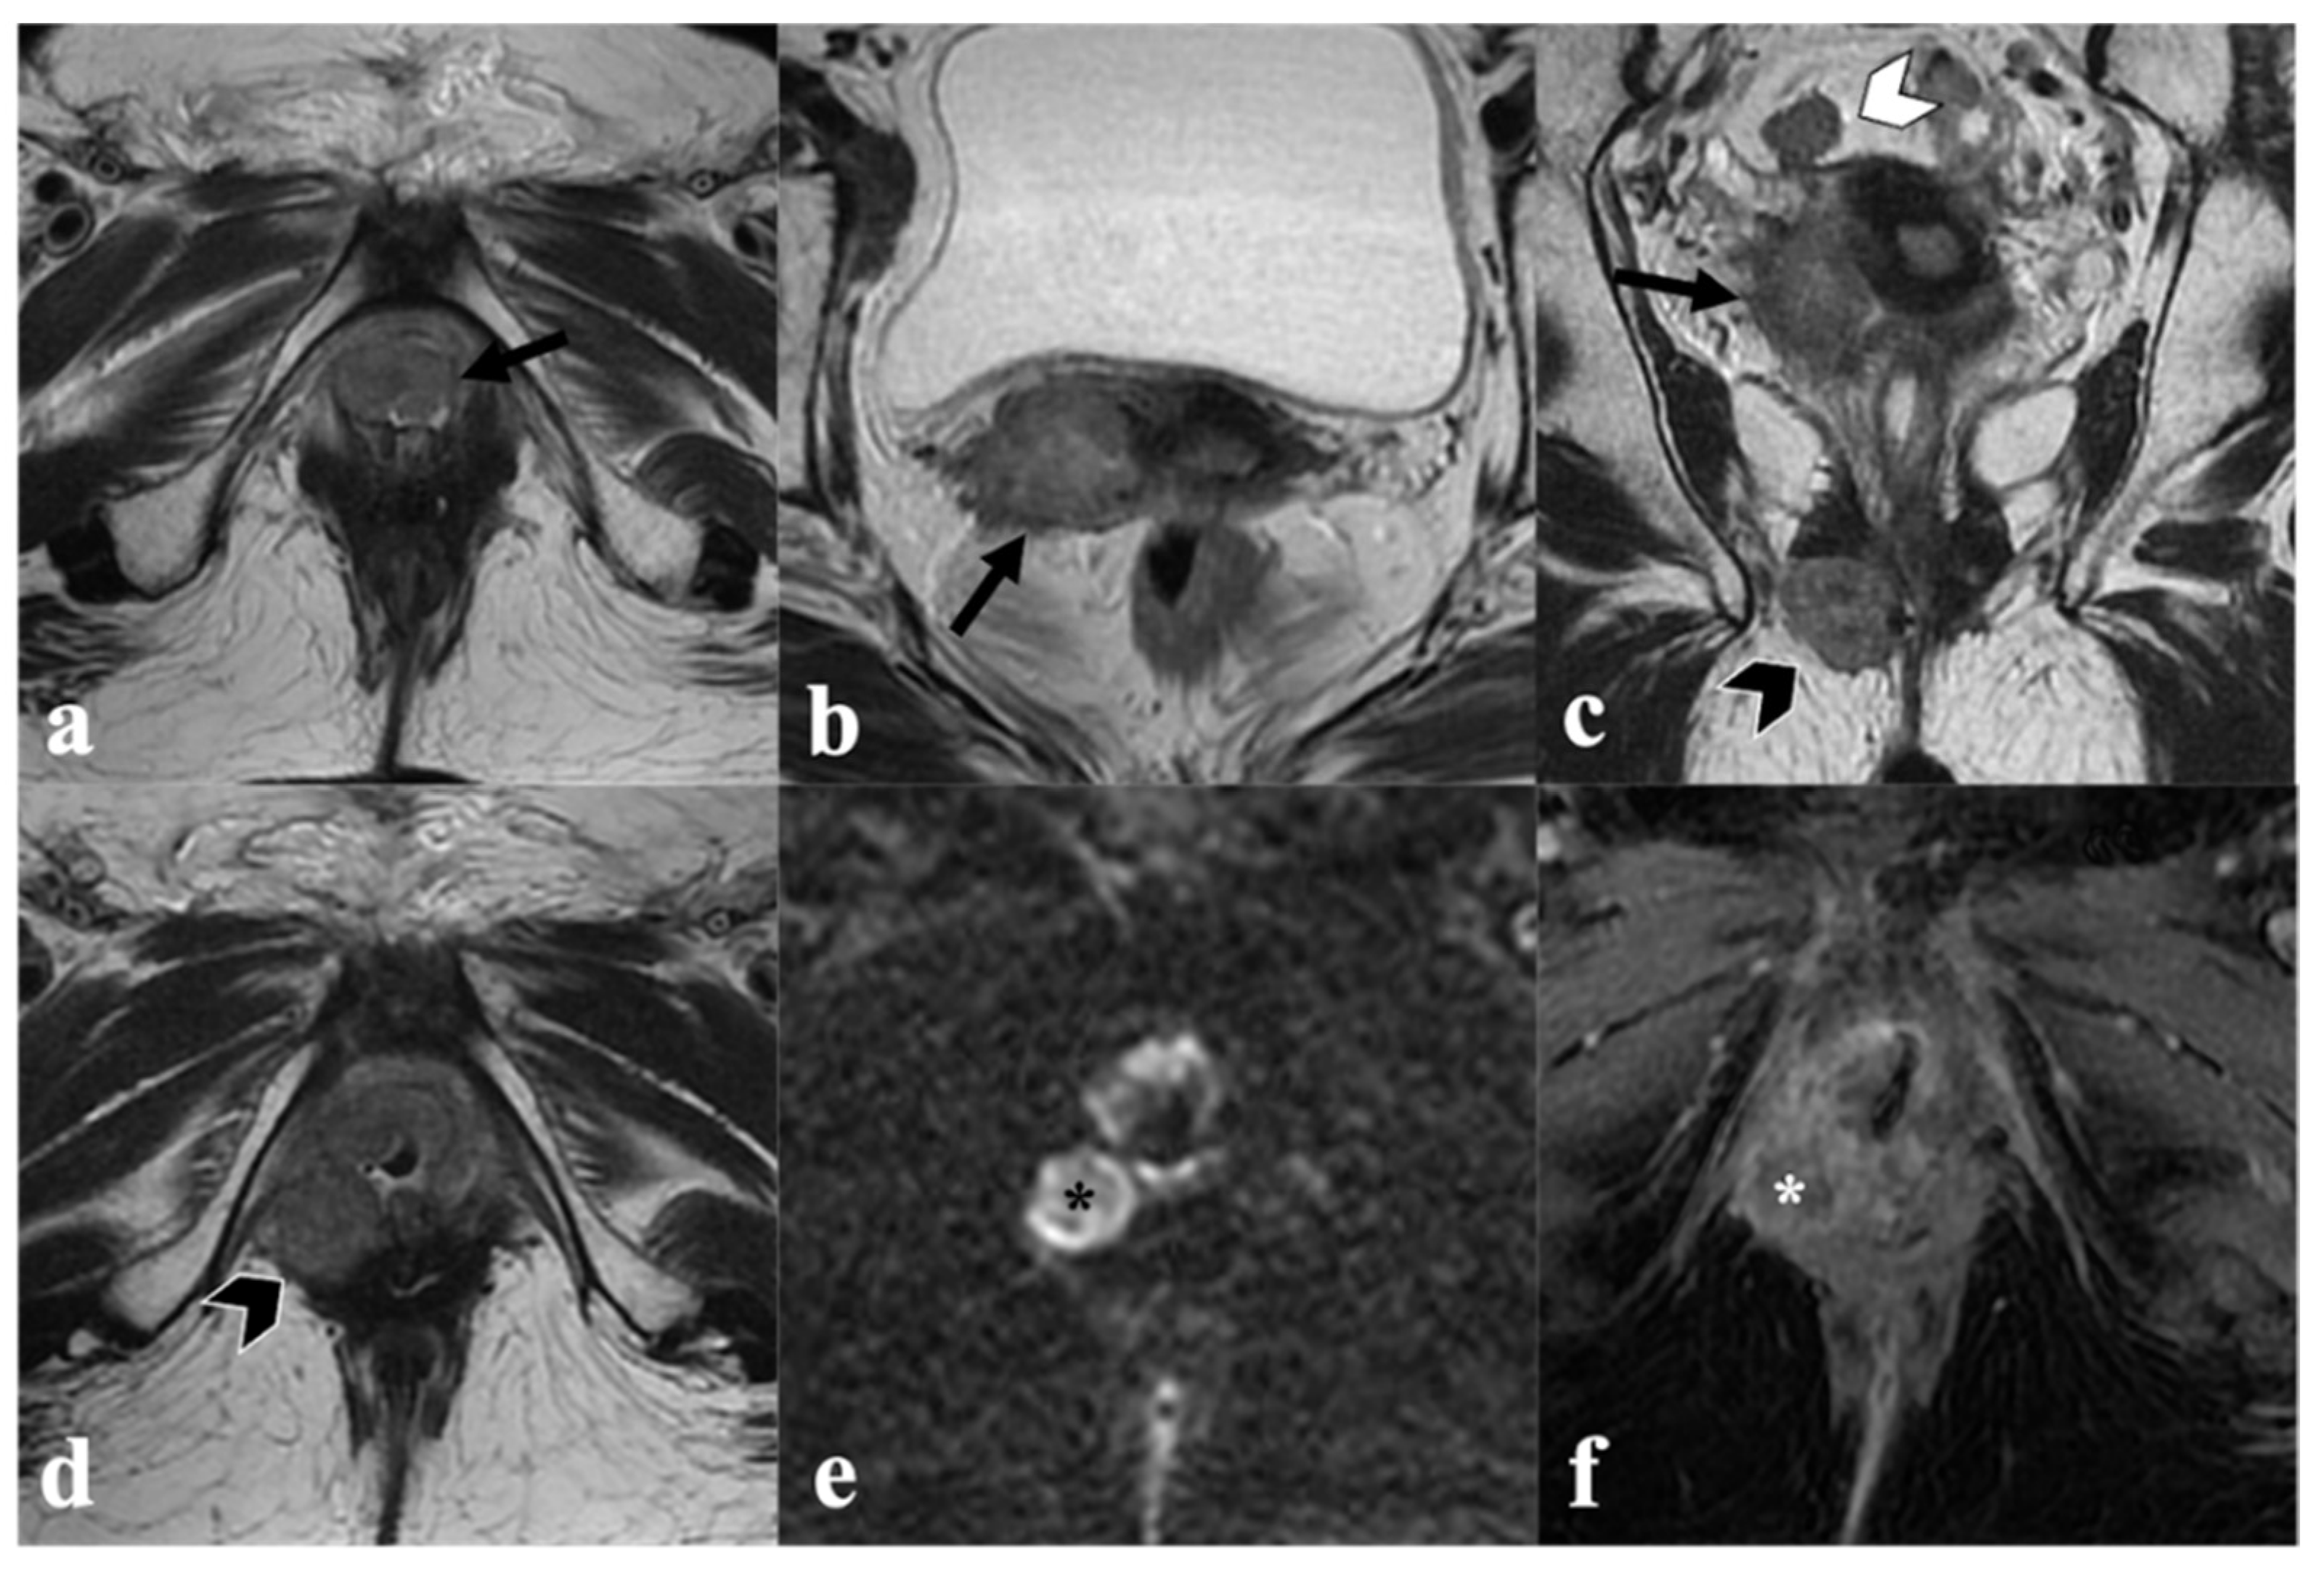

3. MRI Findings of LAVC Prior to CRT

3.1. Vagina

3.2. Urethra

3.3. Anal Sphincter Complex

3.4. Bladder and Rectum

3.5. Inguinal or Pelvic Nodes